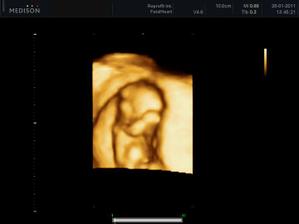

28.1.2011 - Tak máme za sebou velký utz a podle pana doktora je vše v pořádku, ještě musíme počkat na výsledky krve - snad dopadnou dobře. Prcek byl nádhernej, odpovídáme 12+1 a měříme 6,17cm. Nejdříve s náma mimíšek nechtěl moc spolupracovat, stavěl se dokonce i na hlavičku, prostě všelijak, jen né tak, jak by pan doktor potřeboval, tak jsem musela jít na 15 minut pochodovat na hodbu, aby se nám mňous přemístil. Pak se nám ještě chvilku schovával a zakrýval si pusinku ručičkou, ale nakonec se ukázkově natočil a pózoval. Byl to krásný zážitek.